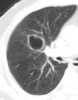

Solitary sharply-outlined cavitary lung lesion

May Be Caused by

Amebic abscess

Amyloidosis

Bacterial abscess

Behçet disease

Bleb

Bronchial cyst

Bronchogenic carcinoma

Bulla

Coccidioidomycosis

Fungal disease

Granuloma

Hamartoma

Hodgkin disease

Hydatid cyst

Intralobar pulmonary sequestration

Isoniazid cyst

Lymphoma

Metastasis

Opportunistic infection

Paragonimiasis

Parasitic disease

Pneumatocele

Pulmonary blastoma

Pulmonary infarction

Rheumatoid nodule

Traumatic cyst

Tuberculosis

Wegener granulomatosis